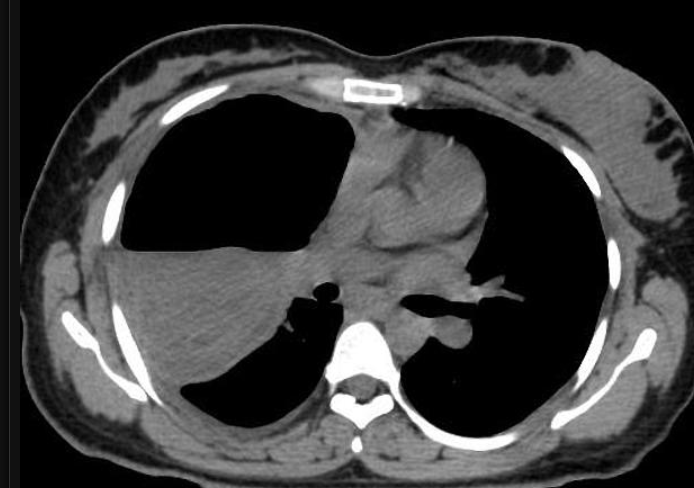

RN a termo.

Cardiomegalia massiva em um neonato com pulmão normal (sem edema alveolar ou intersticial, sem derrame pleural)

Cardiomiopatia neonatal.